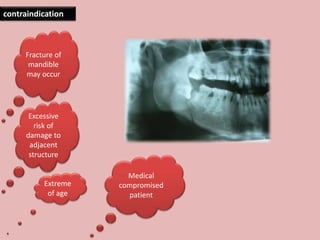

65 year-old with a chronic infection related to an impacted lower third molar. The

patient refused to have her tooth removed. The delay in proper treatment resulted in

progression of the deep bone infection caused by the impacted third molar. This

eventually resulted in a pathologic fracture of the jaw.

Extreme

of age

Medical

compromised

patient

Excessive

risk of

damage to

adjacent

structure

Fracture of

mandible

may occur

contraindication